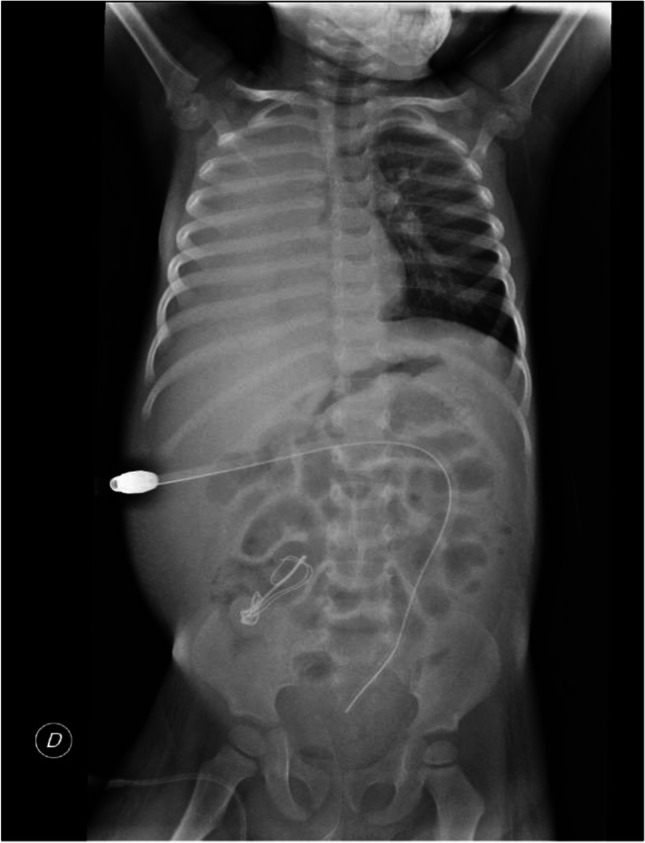

Abstract Image